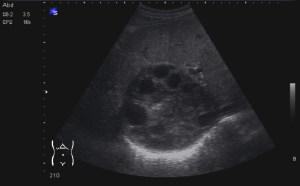

Al llegar al compartimento 6 me encuentro un tendón engrosado de tamaño y aspecto heterogéneo típico de afectación por tendinosis, con líquido en la vaina, te lo señala la imagen con flecha amarilla. Lo recorro y confirmo los hallazgos eje corto y eje largo, hago medidas y compruebo el doppler que marca Neovascularización asociada.

Observa las tres imágenes superiores, son muy ilustrativas, son comparativas de normalidad hallazgos patológicos, el izquierdo claramente patológico y el derecho claramente normal.